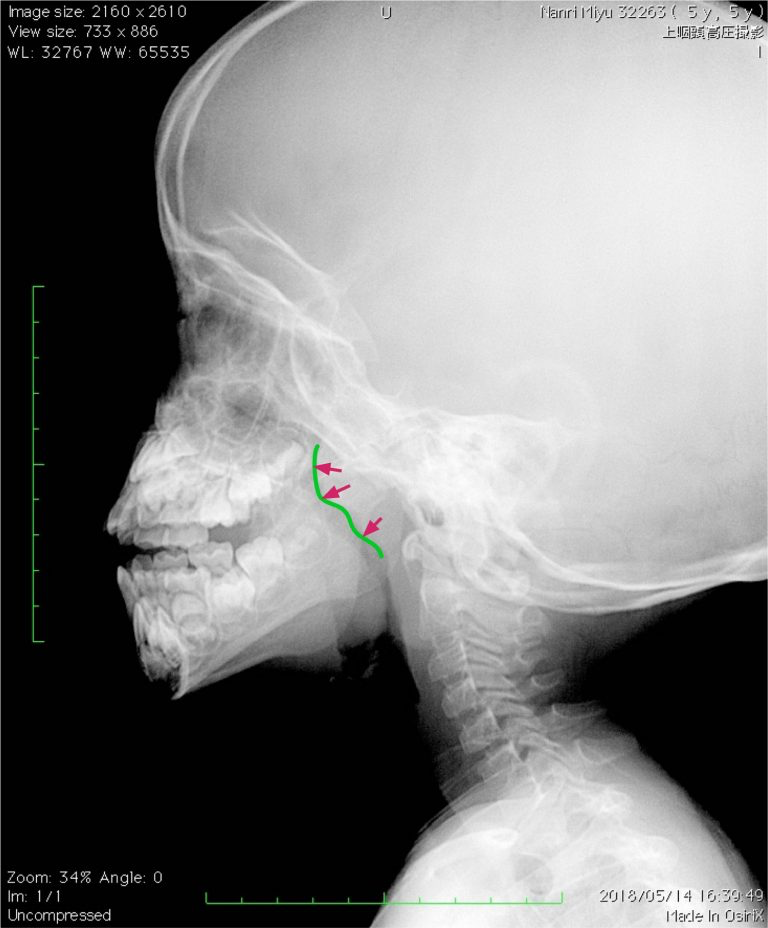

アデノイド増殖症の診断はレントゲン検査で行います。

アデノイドの増殖によって口呼吸をするようになると、下顎の発達が悪くなりいわゆる「アデノイド顔貌」になります。噛み合わせが悪くなる場合もあります。

- アデノイド顔貌:口呼吸に伴い、上の前歯は前に出て下あごが後退するため、下あごが小さく見えます。アデノイドの手術により改善が期待できます。